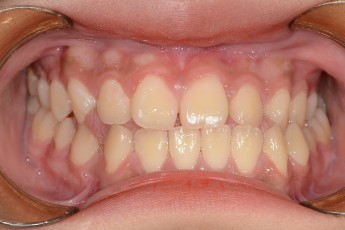

Before

After